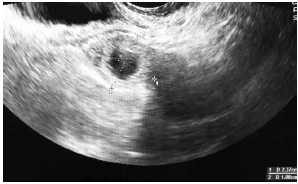

C.V.R.S., 36 anos, G VII P VI (6N) A0, IG cr: 6 semanas,deu entrada no PSGO com sangramento vaginal há cerca de 1 semana. Sem ultrassom prévio. Ao exame físico: especular: colo uterino sem lesões, mínima quantidade de sangue vermelho escuro em fórnice posterior. TV (toque vaginal) bimanual: colo impérvio, grosso, posterior. Ausência de dor à mobilização do colo uterino. Abdome: DB negativo, dor leve à palpação profunda de hipogástrio. Submetida à ultrassonografia transvaginal (imagens a seguir: figuras 1, 2, 3, 4) e beta HCG quantitativo: 9 000 UI/mL. Resultado de beta HCG 24h antes: 7 000 UI/mL.

Figura 3 (zoom de região anexial E; sem visualização de embrião)

Figura 4 (zoom de região anexial E; sem visualização de embrião)